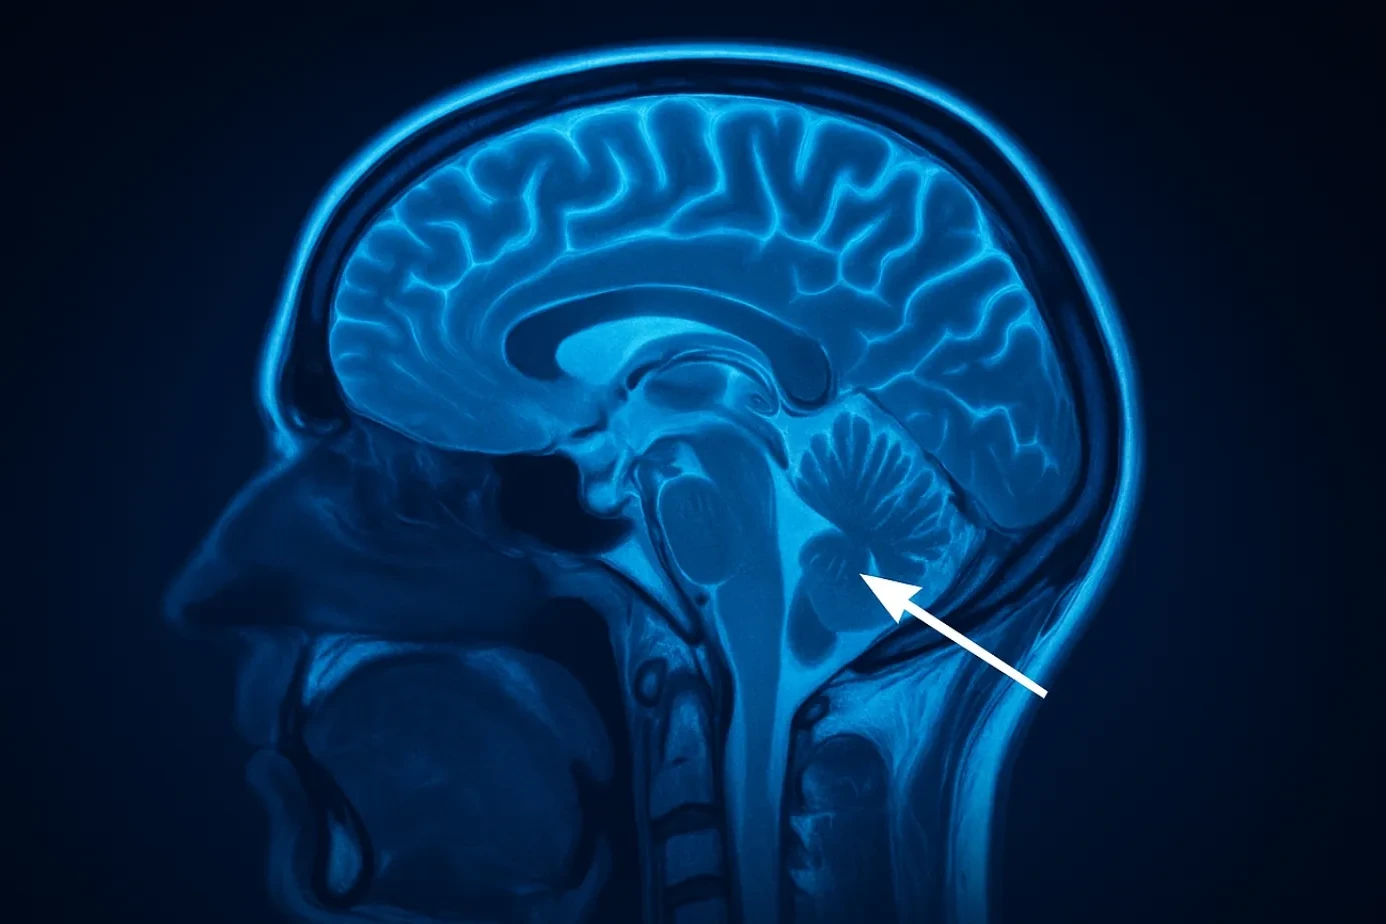

Brain herniation is one of the deadliest conditions in medicine. It happens when part of the brain…

Brain Disorders: Causes, Types, Risks, and Outlook